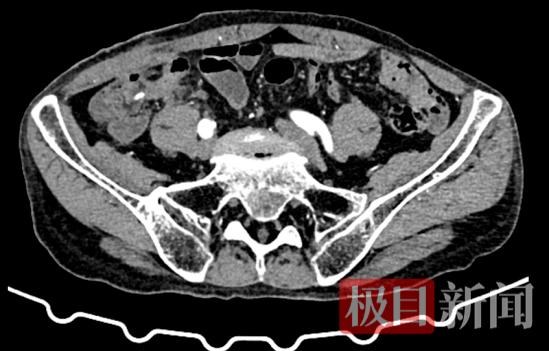

两周前,73岁的患者肖爹爹在外院行阑尾切除手术,术后病理诊断为阑尾恶性肿瘤,遂来到市一医寻求进一步治疗。

为确保治疗精准,医院结直肠癌多学科诊疗(MDT)团队迅速组织会诊,完善相关检查后,结合患者年龄、身体状况及肿瘤分期等情况进行综合研讨,最终确定采用前沿的“经脐单孔腹腔镜下右半结肠切除术”方案,力求在根治肿瘤的同时,最大程度减少手术创伤。